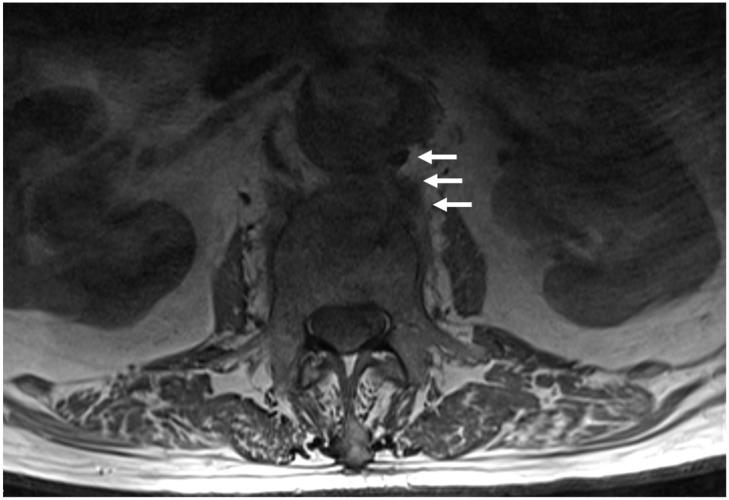

Graft infection following aortic aneurysms repair is an uncommon but devastating complication; its incidence ranges from <1% to 6% (mean 4%), with an associated perioperative and overall mortality of 12% and 17.5-20%, respectively. The most common causative organisms are and ; causative bacteria typically arise from the skin or gastrointestinal tract. The pathogenetic mechanisms of aortic graft infections are mainly breaks in sterile technique during its implantation, superinfection during bacteremia from a variety of sources, severe intraperitoneal or retroperitoneal inflammation, inoculation of bacteria during postoperative percutaneous interventions to manage various types of endoleaks, and external injury of the vascular graft. Mechanical forces in direct relation to the device were implicated in fistula formation in 35% of cases of graft infection. Partial rupture and graft migration leading to gradual erosion of the bowel wall and aortoenteric fistulas have been reported in 30.8% of cases. Rarely, infection via continuous tissues may affect the spine, resulting in spondylitis. Even though graft explantation and surgical debridement is usually the preferred course of action, comorbidities and increased perioperative risk may preclude patients from surgery and endorse a conservative approach as the treatment of choice. In contrast, conservative treatment is the treatment of choice for spondylitis; surgery may be indicated in approximately 8.5% of patients with neural compression or excessive spinal infection. To enhance the literature, we searched the related literature for published studies on continuous spondylitis from infected endovascular grafts aiming to summarize the pathogenesis and diagnosis, and to discuss the treatment and outcome of the patients with these rare and complex infections.